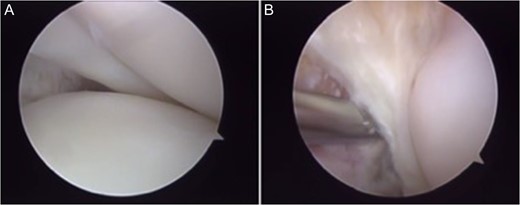

The patient underwent arthroscopic ACL reconstruction using ipsilateral flexor tendons as graft, PCL reconstruction using contralateral flexor tendons as graft and partial meniscectomy (Figs 3–5).

Arthroscopy surgery view during cruciate ligaments reconstruction. Note in (A) and (B) the ligaments absence. The lateral meniscus has not its bone tibial insertion of the posterior horn (*), which continued with the anterior meniscus femoral ligament (Humphry), which was hypertrophied (**). LFC, lateral femoral condyle.